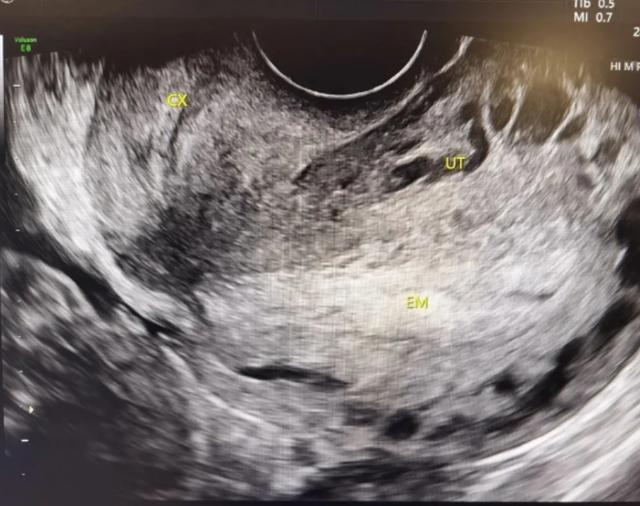

接着,还有四维超声和MRI这些高科技手段来帮忙。四维超声可以直观地显示子宫的形态和结构,而MRI就像个透视眼,能准确地了解假腔的大小、肌层厚度以及是否存在活瓣等关键信息。

(B超显示子宫切口憩室)